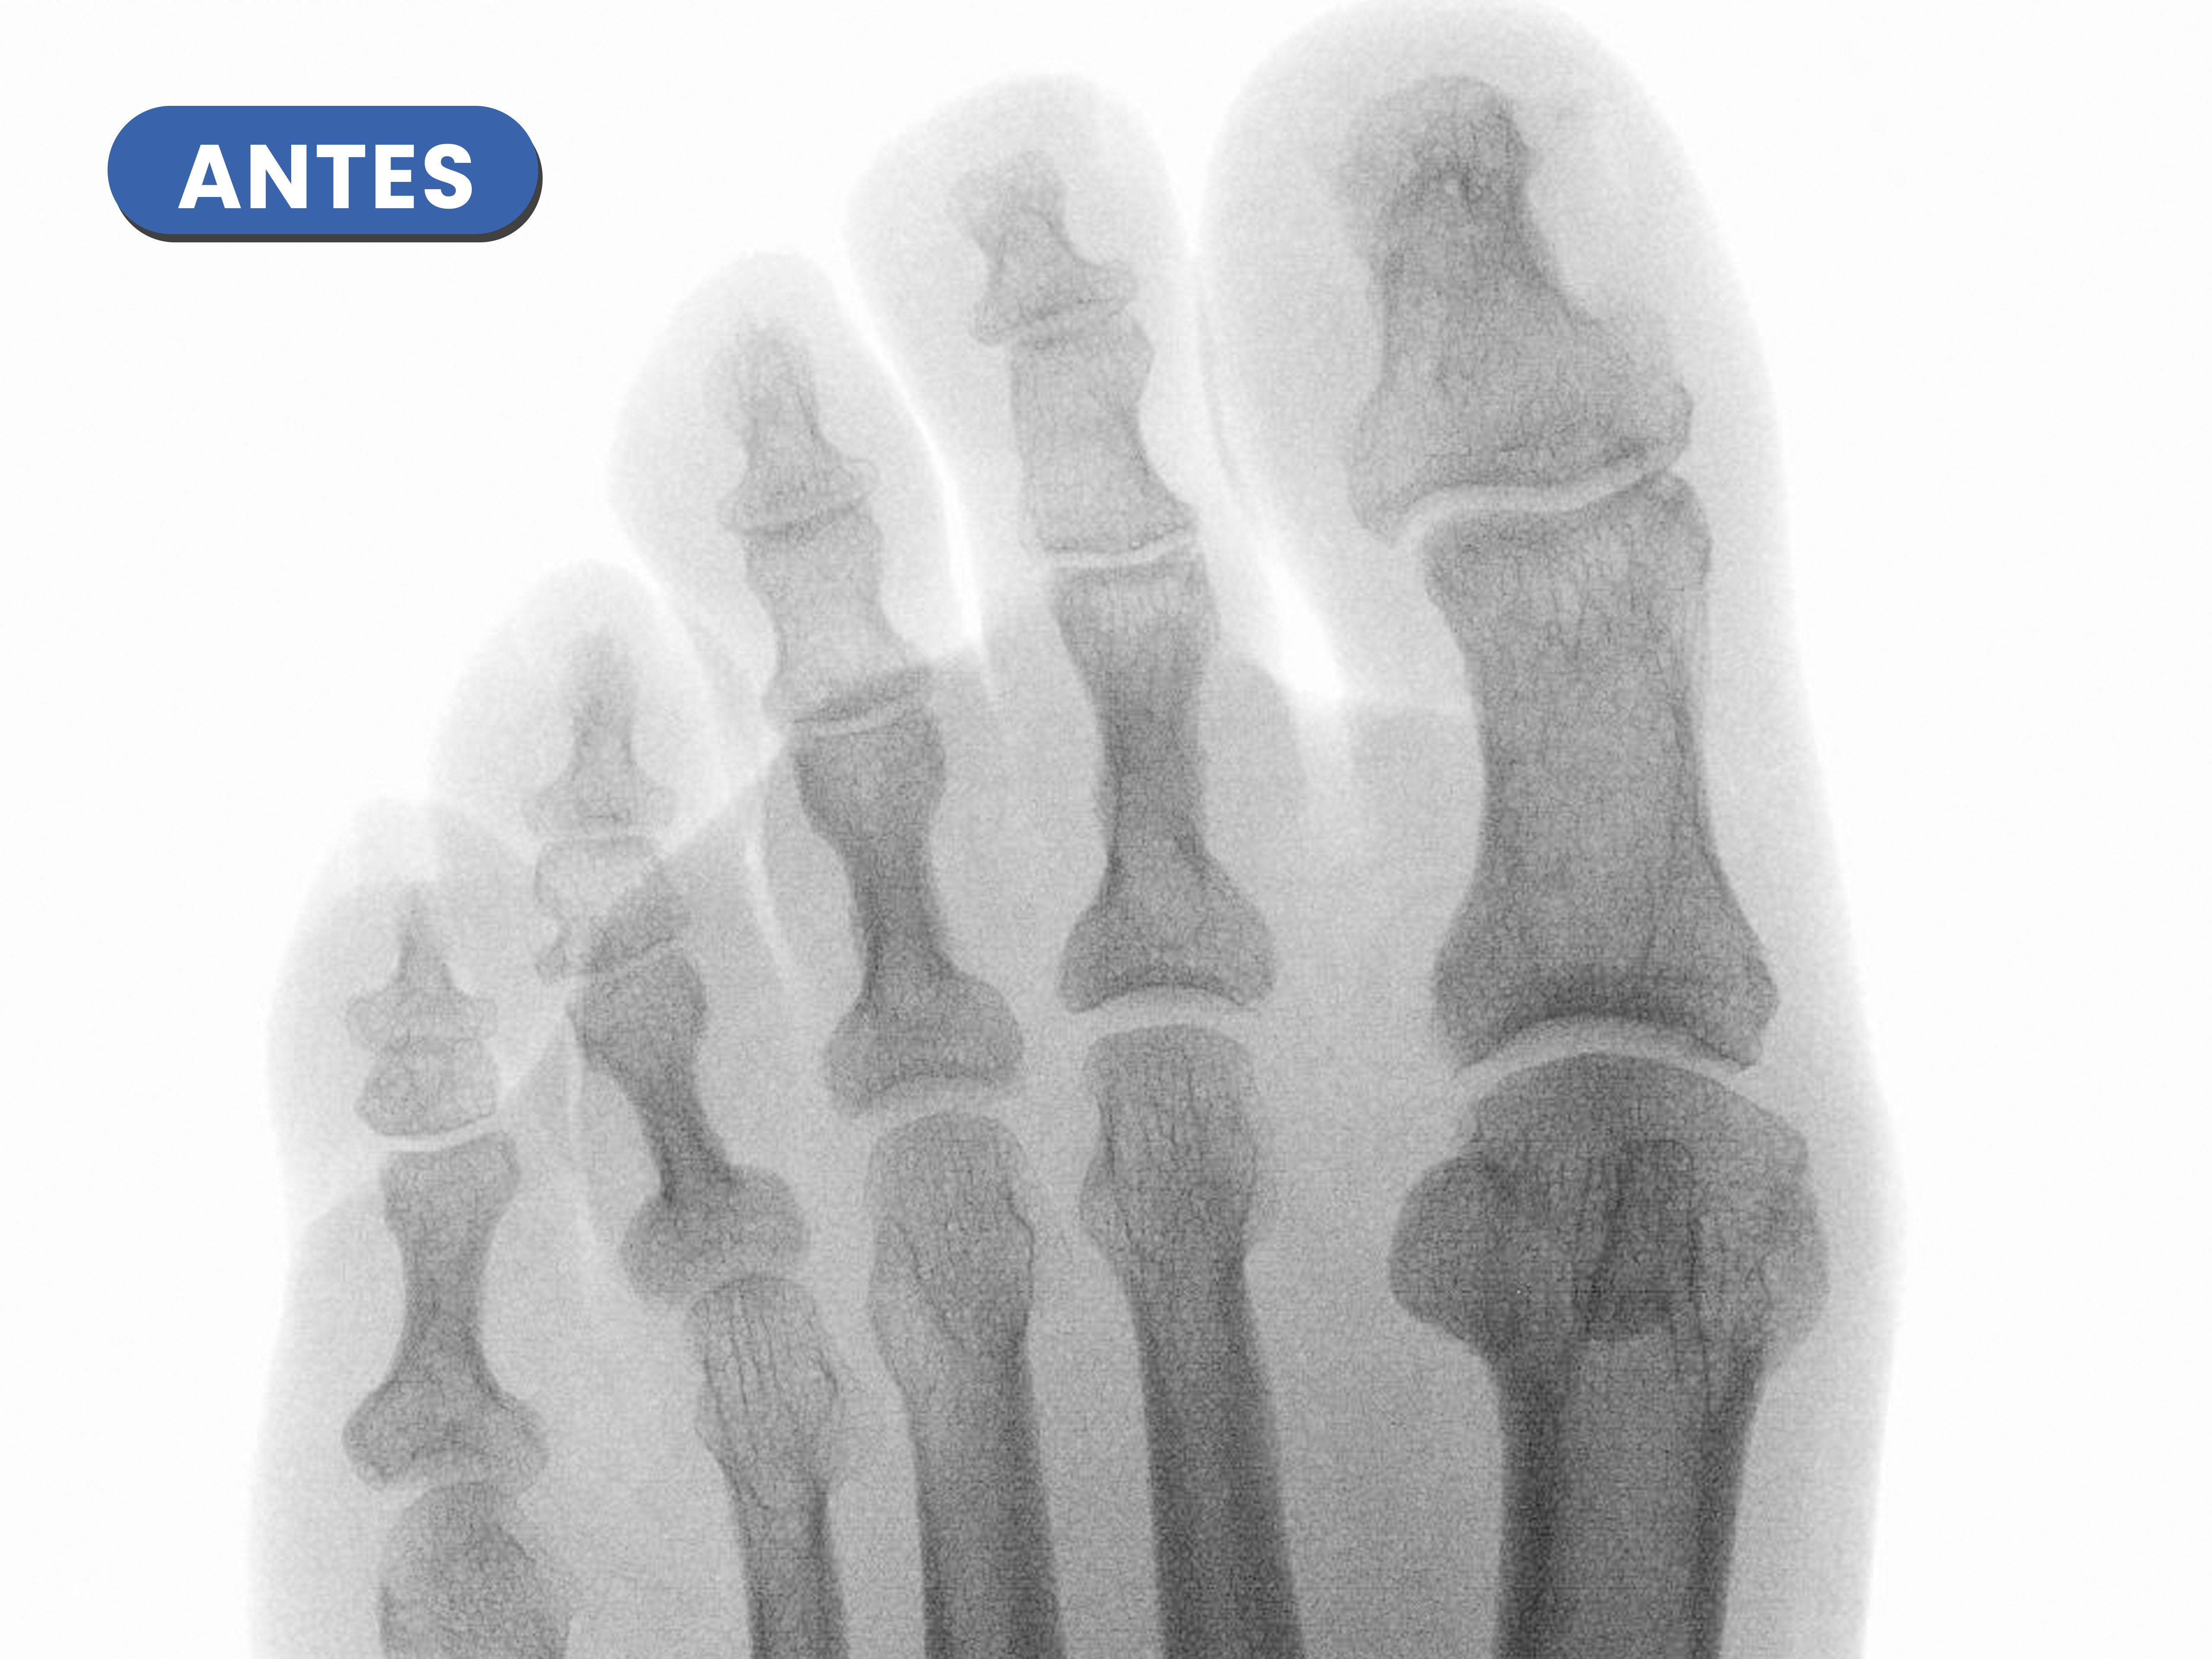

Casos reales resueltos con Cirugía de Mínima Incisión (CMI)

Te mostramos casos reales resueltos mediante cirugía de mínima incisión por el Dr. Rubén Lorca y su equipo.

Mueve las flechas para visualizar el antes y después.

En este caso destaca la corrección metatarsofalángica tras la realización de la osteotomía metatarsal y osteotomía de la falange proximal del cuarto dedo, generandose esa línea o espacio articular entre ambos.